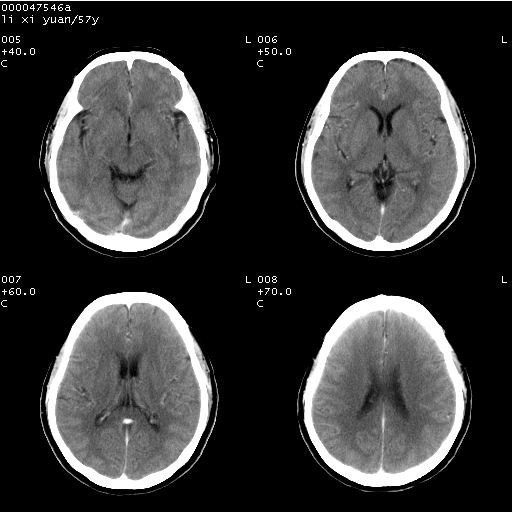

以下是引用zjzjr在2008-4-27 14:23:00的发言:[br]支持慢性炎性肉芽肿可能性大(增强效果较差).

以下是引用余辉在2008-4-27 14:02:00的发言:[br]病灶位于中央沟前方?位于额叶?高密度灶,灶周水肿不明显,病灶似沿脑沟走行,强化明显,局部层面呈现环状强化,考虑1脑表面血管性疾病,如血管瘤,血管扩张,灶内血栓形成,其次考虑肿瘤如脑膜瘤、转移瘤,胶母等

以下是引用形影不离在2008-4-27 14:13:00的发言:[br]考虑胶质瘤可能性大,不排除慢性炎性肉芽肿。建议mri检查。